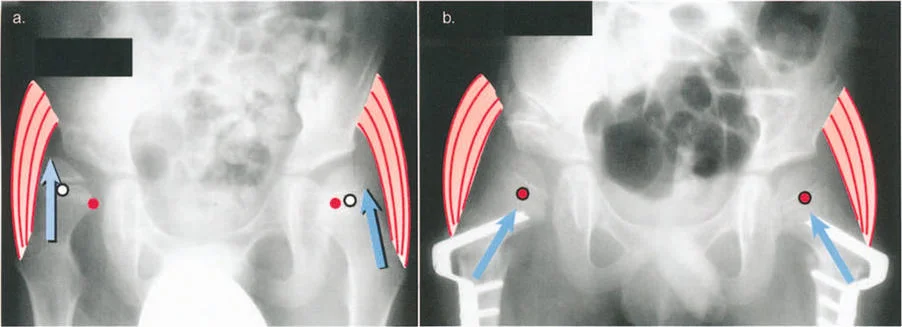

أمثلة أخرى رئيسية للتشوهات الديناميكية تشمل "الورم الفخذي المفرط" (Severe Femoral Anteversion) و "الورك الأفحج" (Coxa Vara). في كلتا هاتين الشذوذات المعمارية، يتم تقصير الطول الفيزيائي لذراع الرافعة لعضلات المبعدة (Abductor muscles) بشكل مرضي بسبب التشوه العظمي نفسه. قد تكون عضلة الألوية الوسطى (Gluteus Medius) صحية تمامًا، ومعصبة جيدًا، وقادرة على توليد قوة بيولوجية طبيعية، لكنها تعاني من خلل وظيفي سريري عميق لأن ميزتها الميكانيكية قد سُلبت بسبب الهندسة الهيكلية المتغيرة. هذه الفئة الفرعية المحددة من الأمراض تُعرف باسم "تشوه في طول ذراع الرافعة".

- الورك الأفحج (Coxa Vara): تشوه خلقي أو تطوري في عظم الفخذ يؤدي إلى تقصير ذراع الرافعة لعضلات الورك المبعدة، مما يضعف قدرتها على تثبيت الحوض.

- عرج ترندلنبورغ (Trendelenburg Lurch): في حالات ضعف عضلات الورك المبعدة (مثل الورك الأفحج)، يميل الحوض إلى السقوط على الجانب المقابل أثناء الوقوف على ساق واحدة، مما يؤدي إلى مشية متمايلة.

التصوير الطبي

تُعد الأشعة السينية والتصوير المقطعي المحوسب والرنين المغناطيسي أدوات حاسمة لتحديد التشوهات الهيكلية وتقييم المحاور الميكانيكية.

- الأشعة السينية (X-rays):

- الأشعة الثابتة: تُستخدم لتقييم التشوهات العظمية الواضحة، والتئام الكسور، وحالة المفاصل.

- الأشعة مع تحمل الوزن (Weight-bearing X-rays): تُظهر كيف تتصرف المفاصل والعظام تحت الضغط الطبيعي للجسم، وهو أمر حيوي لتقييم التشوهات الديناميكية.

- أشعة الأطراف الطويلة (Long Leg Films): تُؤخذ هذه الأشعة من الورك إلى الكاحل في صورة واحدة لتقييم المحور الميكانيكي الكامل للطرف السفلي وتحديد أي انحرافات.

- التصوير المقطعي المحوسب (CT Scans): يوفر صورًا ثلاثية الأبعاد للعظام، وهو مفيد بشكل خاص لتقييم التشوهات الالتوائية (مثل الورم الفخذي المفرط) وتحديد موقع مركز دوران الانحراف (CORA) بدقة.